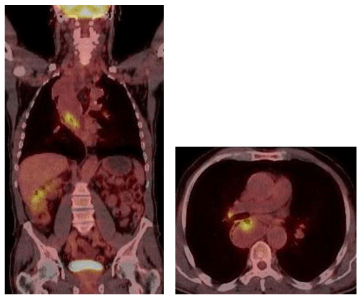

Diagnostic imaging was performed including a Computed Tomography (CT), a cine esophagography and a Fluorodeoxyglucose (FDG) Positron Emission Tomography (PET). The multi-slice CT of the chest and abdomen was performed in 2 x 64 x 0, 6 mm Collimation (Siemens Somatom Definition AS +), with oral and i. V contrast medium application. CT scan revealed a polylobulated mass (tumour size of 330x85x65 mm) of the esophagus with fatty and soft tissue density, extending from the thoracic inlet to the distal esophagus and causing a tracheal compression as well as a compression of the right main stem bronchus (Figure 3). There were no metastatic lesions detected in the CT. In the PET only the tumour masses in the middle part of the mediastinum showed a FDG uptake with a maximal Standard Uptake Value (SUV) of 7,4 (Figure 4).

Figure 4: PET/CT: FDG positive mass in the middle part of mediastinum with a maximum standardized uptake value (SUVmax) of 7, 4.